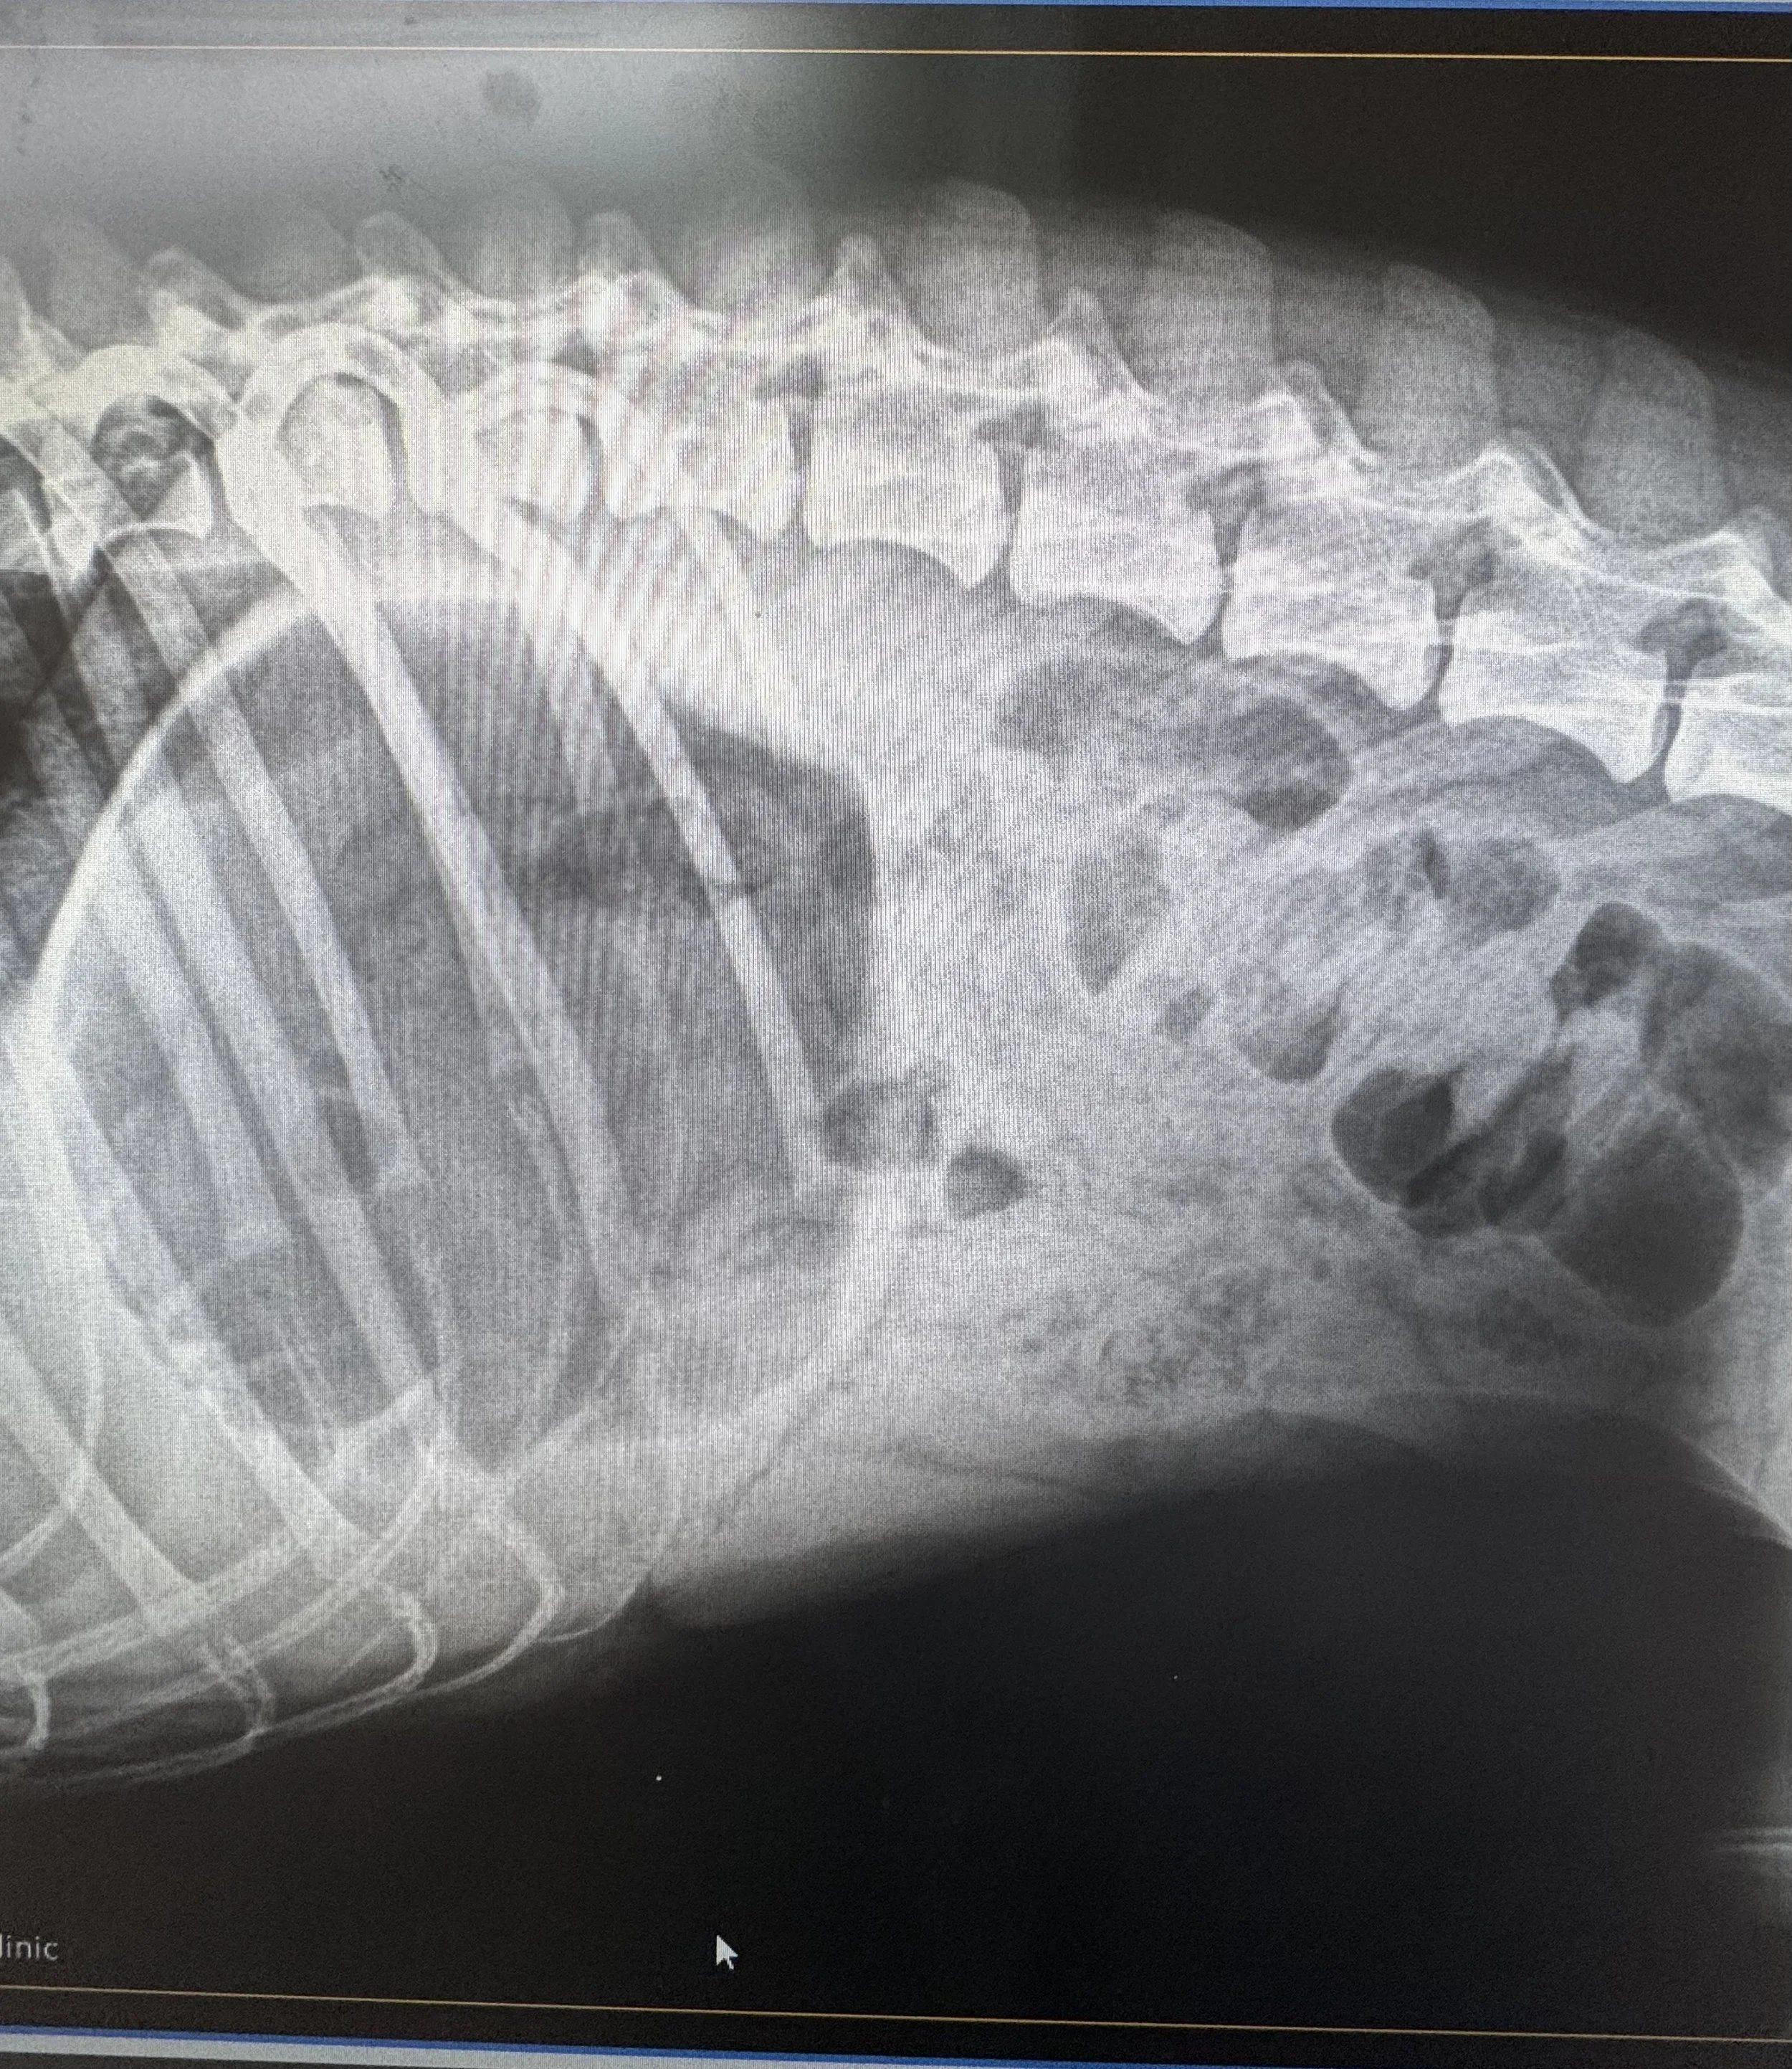

Osteochondritis Dissecans (OCD) in Dogs: Causes, Symptoms, and Treatment

Osteochondritis dissecans (OCD) is a developmental orthopedic disease that affects the joints of young dogs and often causes limping and pain. Learn the signs and treatment options.